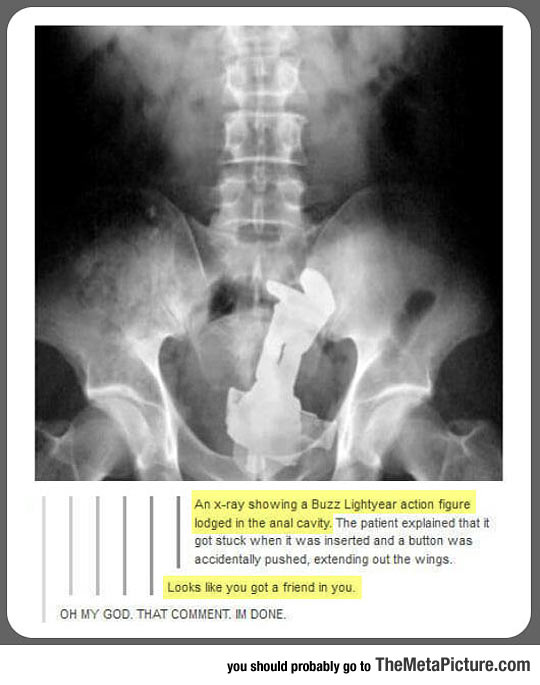

cool-X-Ray-Buzz-Lightyear

540 × 685